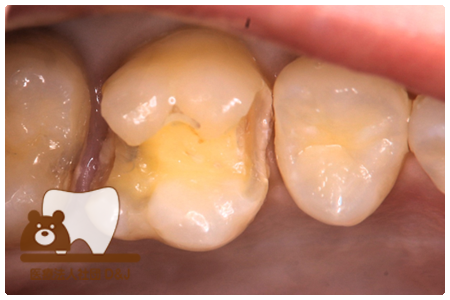

症例3フリジルコニアクラウン 左上6

治療前

治療後

59歳 男性

- 治療内容

- 虫歯で大きく失われた歯に対して、土台としてファイバーコアを使用し、その上にフルジルコニア製の被せ物を装着しました。見た目と強度を両立した自由診療の治療です。

- 治療期間

- 根の治療含めて3カ月半

- 費用

- 自費

フリジルコニアクラウン:77,000円(税込)

(R8.2月時点)

- その他の治療の費用は含まれておりません。

- リスク・副作用

- 強い力が加わると割れる可能性があります。また、噛み合わせや歯ぎしりの影響で脱離することがあります。